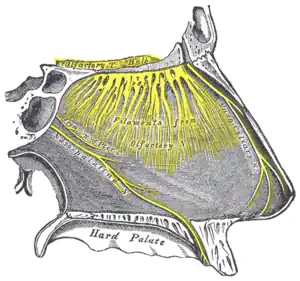

Les fosses nasales constituent la partie supérieure de l’appareil respiratoire, elles sont importantes pour réchauffer et assainir l'air inhalé. De plus, elles contiennent les organes impliqués dans l'olfaction.

Vascularisation et innervation

La vascularisation est riche. Elle est assurée par plusieurs sources, d'une part les branches de l'artère carotide externe comme l'artère sphénopalatine ; d'autre part des branches de l'artère carotide interne comme les artères ethmoïdales antérieures et postérieures qui présentent des anastomoses avec le réseau carotidien externe. Chez certains animaux comme les chiens, le lit capillaire passant par les fosses nasales aide à refroidir la circulation sanguine cérébrale.

L'innervation sensitive provient des deux premières branches du nerf trijumeau.

L'innervation végétative est complexe. Les fibres sympathiques sont vasoconstrictrices, tandis que les fibres parasympathiques sont vasodilatatrices.

Sur les côtés latéraux on a trois cornets qui offrent une résistance à l'écoulement de l'air et le dirigent vers l'épithélium olfactif en haut.

L'organe voméronasal, situé en arrière sur le septum, a un rôle dans la détection de phéromones, excepté chez l'homme où cet organe est vestigial.

Les cornets sont également riches de récepteurs nerveux sensibles au flux aérien (liés au circuit nerveux « trigéminé », le cinquième nerf crânien).

Ces récepteurs détectent la pression et la température et aide ainsi, par un mécanisme encore inconnu, à l'activation des récepteurs d'odeurs situés dans les régions supérieures du nez.

Les cornets supérieurs protègent le bulbe olfactif et sont également innervés avec une multitude de terminaisons nerveuses olfactives qui se prolongent quelque part dans les cornets moyens.